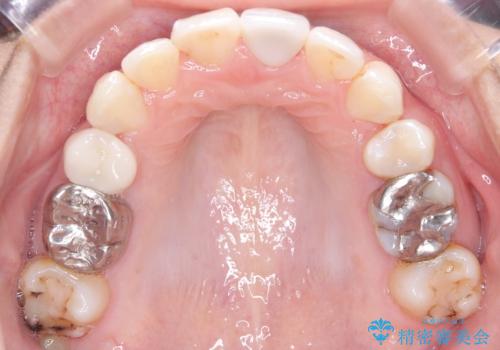

- 口元が出ていることを気にされて来院されました。精密な検査の結果、歯列全体のスペースが不足していることが判明。患者様のご希望である「口元を下げたい」というご要望を叶えるため、上下左右の小臼歯を抜歯し、そのスペースを利用して前歯を奥へ移動させる治療計画を立案しました。また、仕事上、目立つ矯正装置を避けたいというご希望から、上顎に裏側矯正、下顎に表側矯正を組み合わせたハーフリンガル矯正を提案しました。

今回の矯正治療では、口元を大きく下げるため、上下左右の小臼歯を抜歯しました。装置には、上顎は歯の裏側に装着する裏側矯正(舌側矯正)を、下顎は透明で目立ちにくい審美ブラケットを使用するハーフリンガル矯正を選択。これにより、治療中も他人の目を気にすることなく、ストレスなく過ごしていただけました。抜歯によってできたスペースを有効活用し、歯列全体を後方へ移動させることで、口元の突出感を解消。治療の結果、口元がすっきりと整い、自信のある美しい横顔を獲得していただけました。